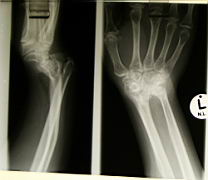

Madelung deformity -- a congenital problem with bone fusion in the arm |

Patient with Madelung deformity -- worse on the left since she is left-handed. |